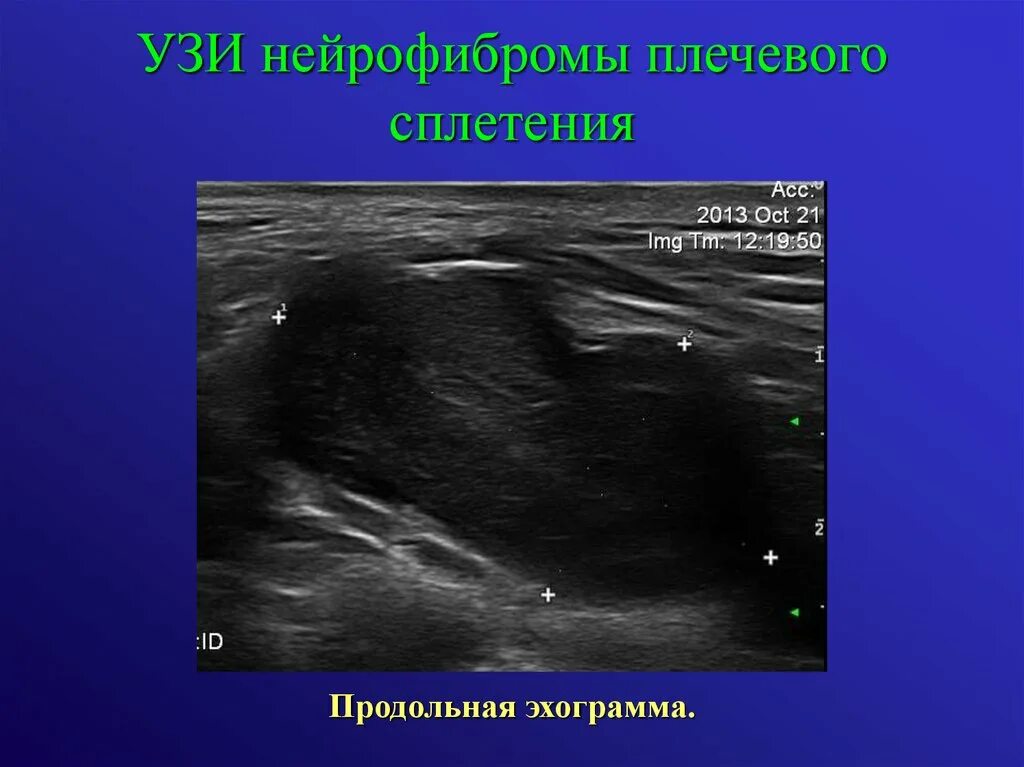

Узи нервов сделать в москве